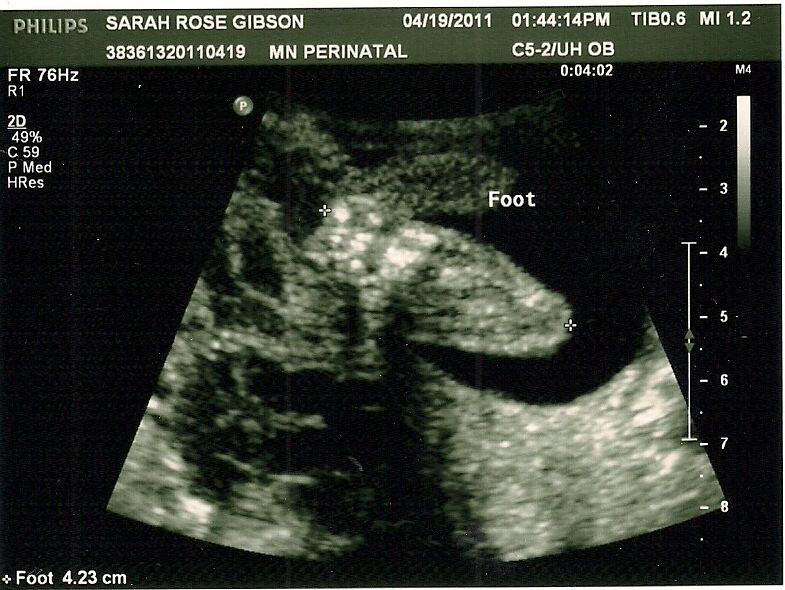

Tiny foot!